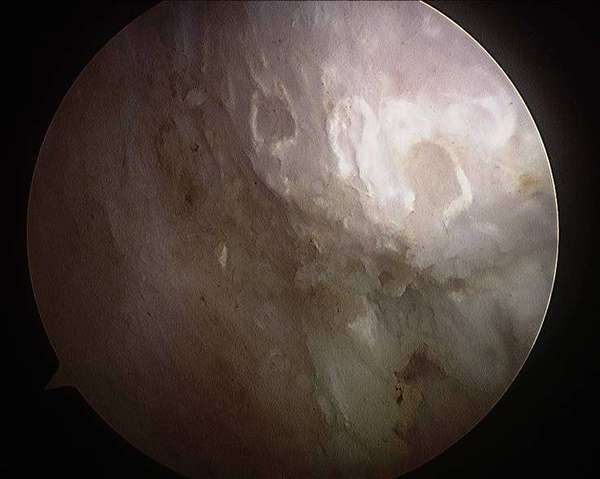

关节镜下见股骨头颈前外侧骨赘